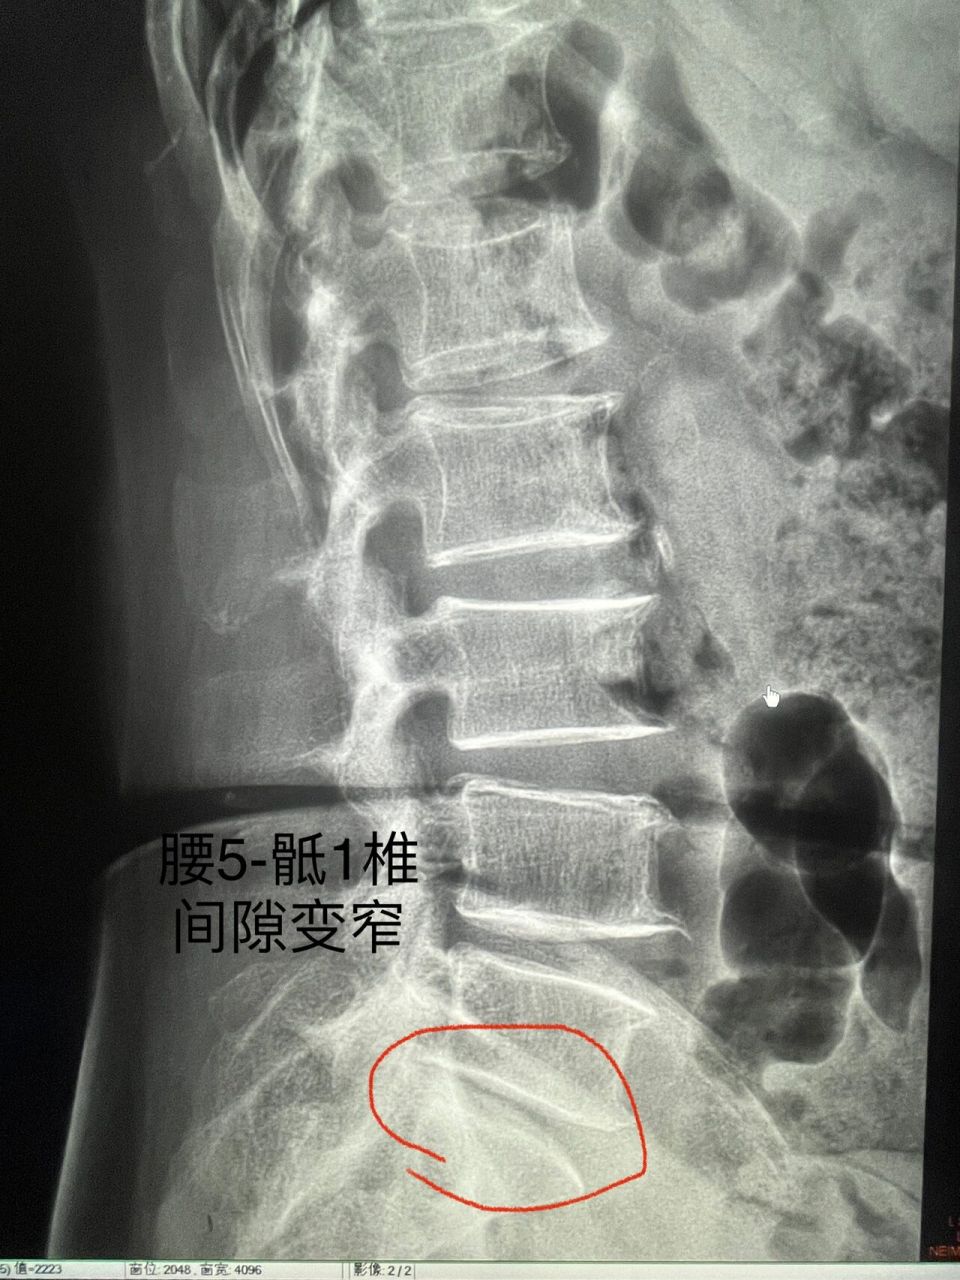

影像读片|第21566天|腰椎退行性改变 今天给大家带来腰椎相关病变